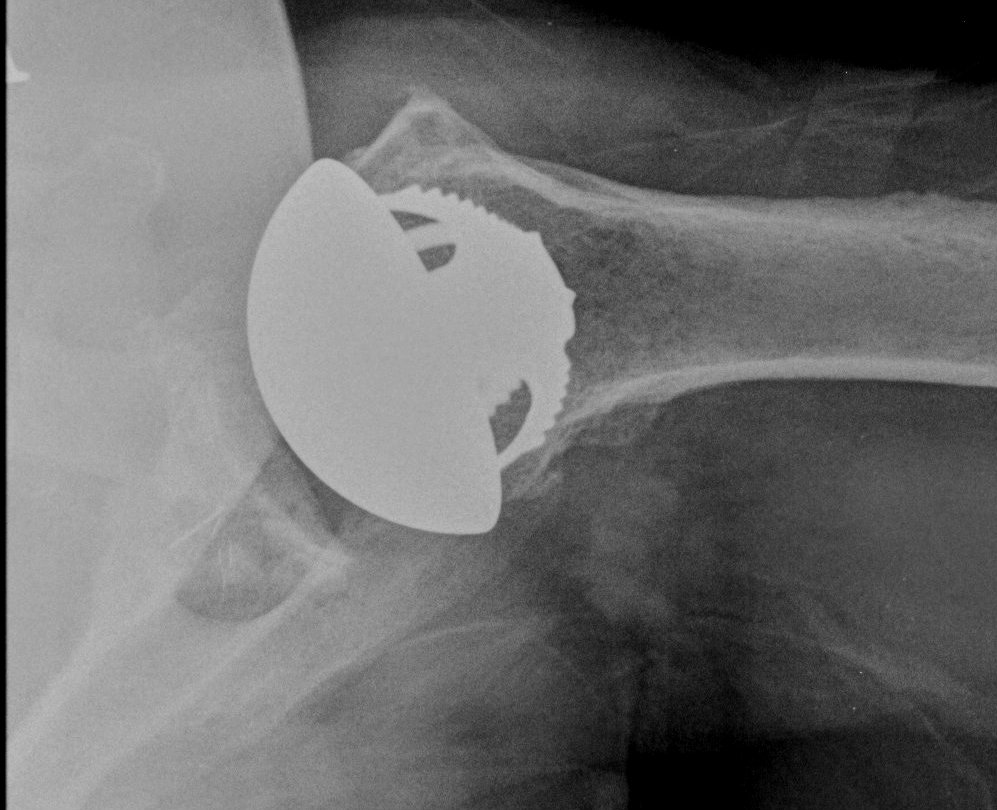

Glenoid component

Glenoid center point crucial

Vault is a triangle

- pilot hole critical

- must not penetrate vault with keel or peg drilling

- get vault perforation / blowout

- cannot pressurise cement

Vault blowout / perforation

1. Freehand technique

- identify center of glenoid articular surface

- glenoid center point slightly inferior and anterior to center of the articular surface glenoid

- match inclination of glenoid

- insert guide pin aiming anteriorly

2. 3D CT templating

- templates glenoid component

- creates guide that matches glenoid

- allows placement of guide pin

Insert guide pin

- ream only articular cartilage

- preserve subchondral bone

- reamers often semi-circle to aide insertion and removal

Ream peg / keel

- ensure no blowout with arthroscopy probe